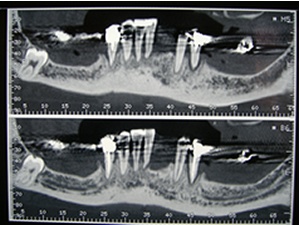

L'examen scanner en mode "panoramique"

Nous souhaitons proposer une solution fixe bien que ces clichés nous montrent qu'il est impossible de poser des implants au delà des trous mentonniers.

L'examen scanner nous confirme la raréfaction osseuse.

Seules les coupes au niveau inciso-canin sont des sites exploitables pour la pose des implants.

Au delà du trou mentonnier il n'y a plus de hauteur osseuse disponible. Notez la position du trou mentonnier par rapport à la crête.